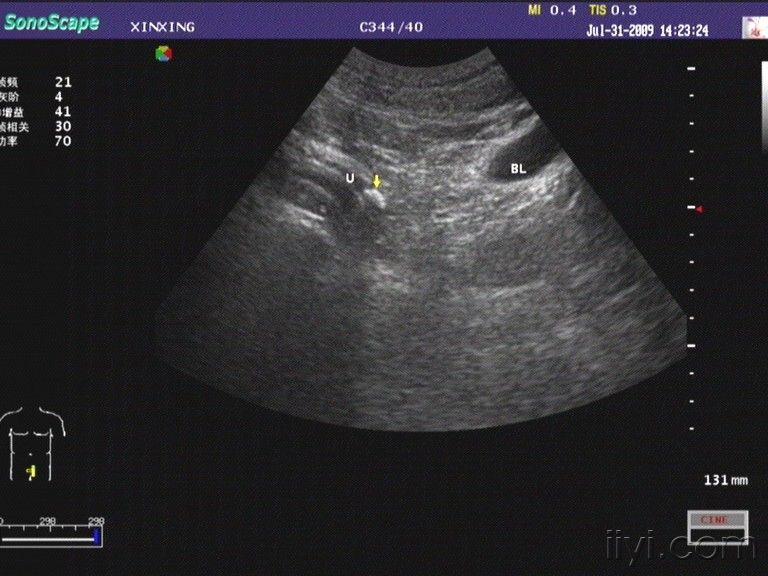

输尿管末端结石 - 超声医学讨论版 - 爱爱医医学论坛

输尿管结石腹部探头和高频探头图像对照 - 超声医学版

输尿管扩张超声图片

输尿管结石

超声图像